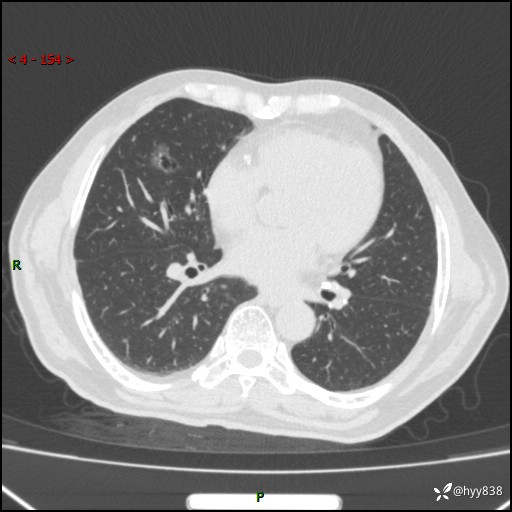

胸部CT平扫(2024.2)